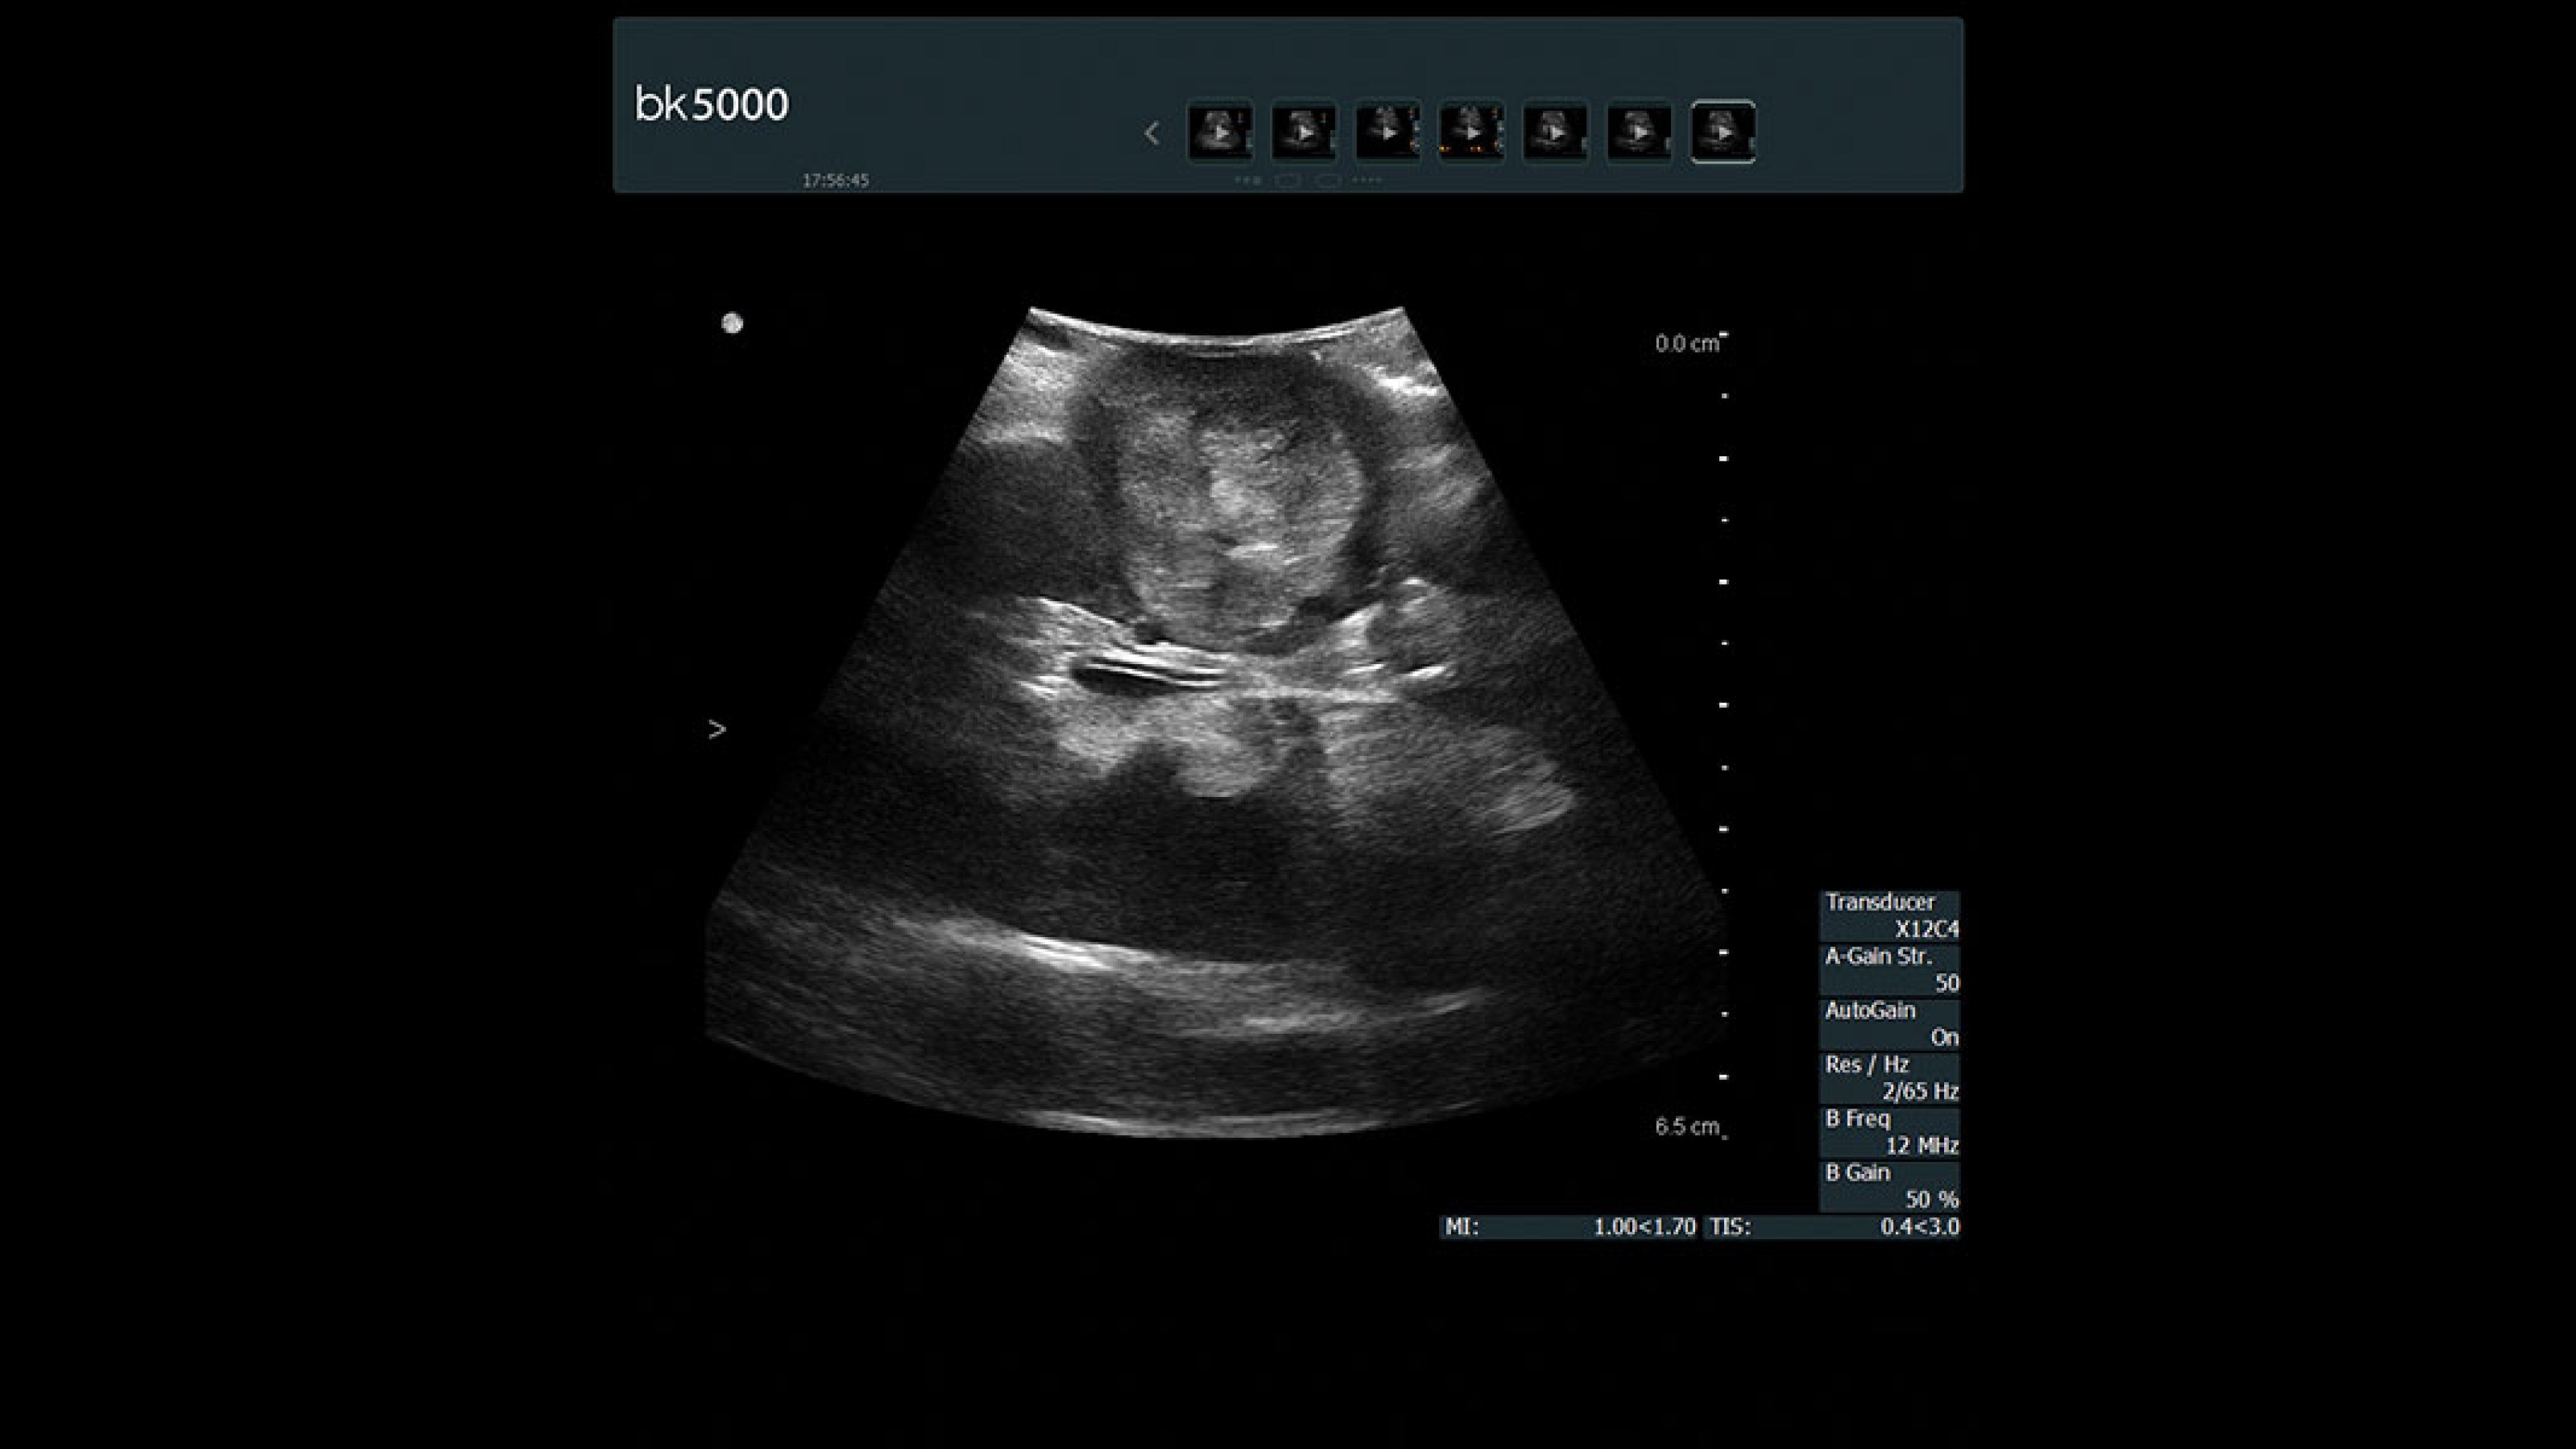

The bk5000 surgical system advances intraoperative surgical procedures by helping you navigate and identify lesions and anatomical structures in real-time. This is particularly important as the data obtained from a preoperative CT or MRI scan can be outdated at the time of surgery.

• Highest quality images: Clearly see the margins of a lesion and determine the best course of action.

• Advanced graphics processing technology: Provides immediate, auto-optimized images for faster information retrieval.